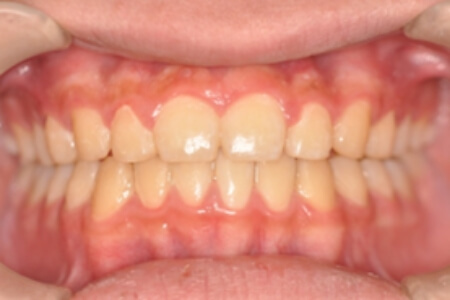

動的治療終了時

症例 症例 症例 症例 症例

治療としては、非抜歯の上、マウスピース矯正装置(インビザライン)で配列を行いました。顎間ゴムの協力もあり、咬み合わせがきれいに改善されました。

治療期間は1年11か月でした。